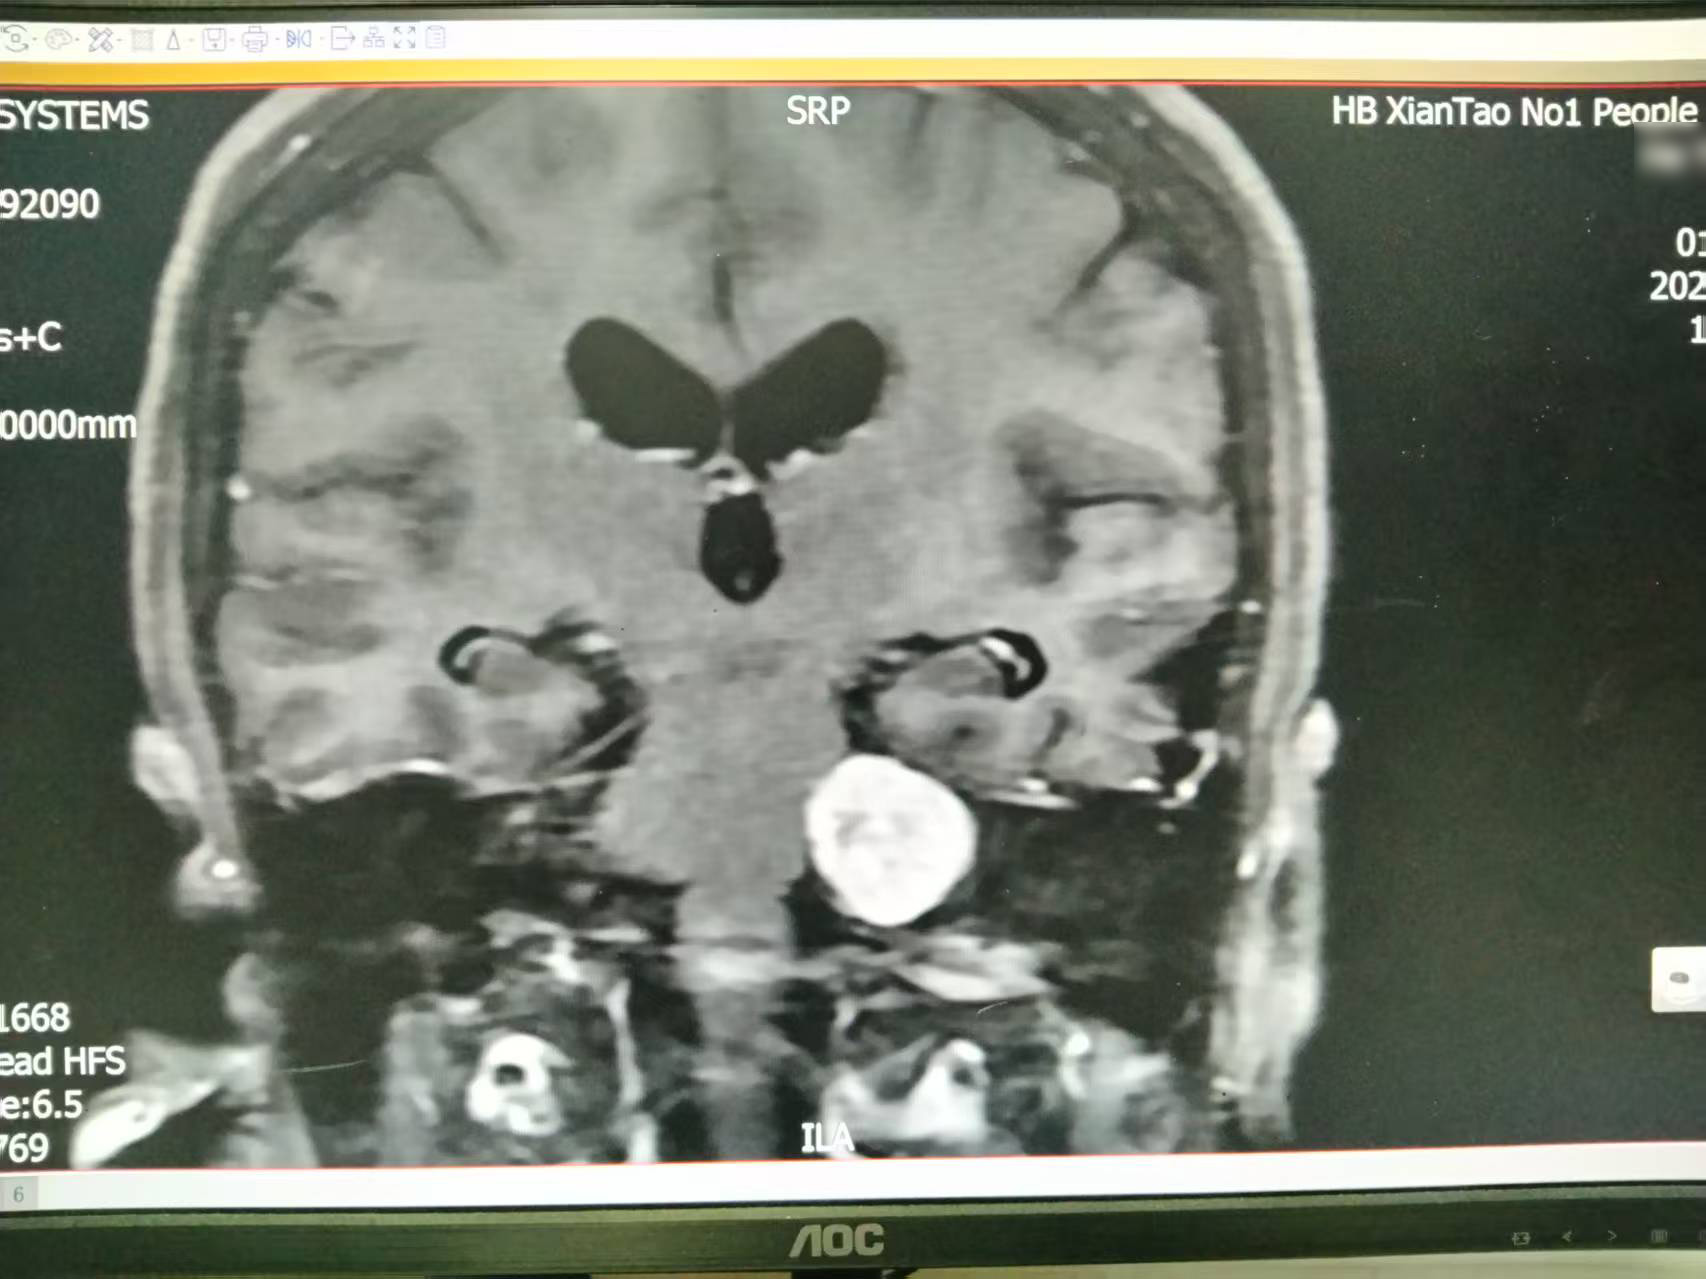

患者向女士(化名)一周前发现颅内肿物后入院治疗。经过颅脑MRI检查,显示其左侧桥小脑角区存在占位性病变,考虑听神经瘤可能。此时肿瘤已引发听力减退、头晕等明显症状。由于肿瘤位置深、紧邻重要神经血管,若不及时进行手术干预,患者将面临进行性听力丧失、面神经损伤等严重并发症的风险。

▲术后复查